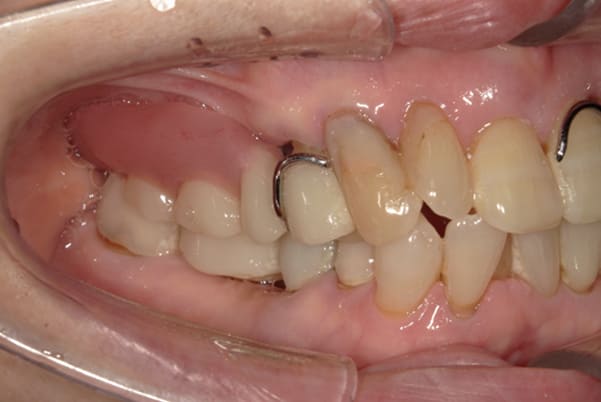

ご自身の歯に負担の少ないバネ、また見た目も改善

ご自身の歯に負担の少ないバネ

銀歯からセラミック歯に

バネをかける歯は繋げることで強度を増し、歯への負担を軽減し、歯の寿命を長くする設計へ。

バネがかかる歯の被せ物は、歯への負担を減らし、入れ歯が動きにくいようになる形態をあらかじめ付与することで、より入れ歯の機能が高まります。

治療を行う際、被せ物や入れ歯は、別々に考えるのではなく、一口腔単位としてお口全体のことを考え最良の治療計画を立てることが歯の寿命、機能効果を向上させるため、専門医としてこのことは常に心掛けて治療を行っています。